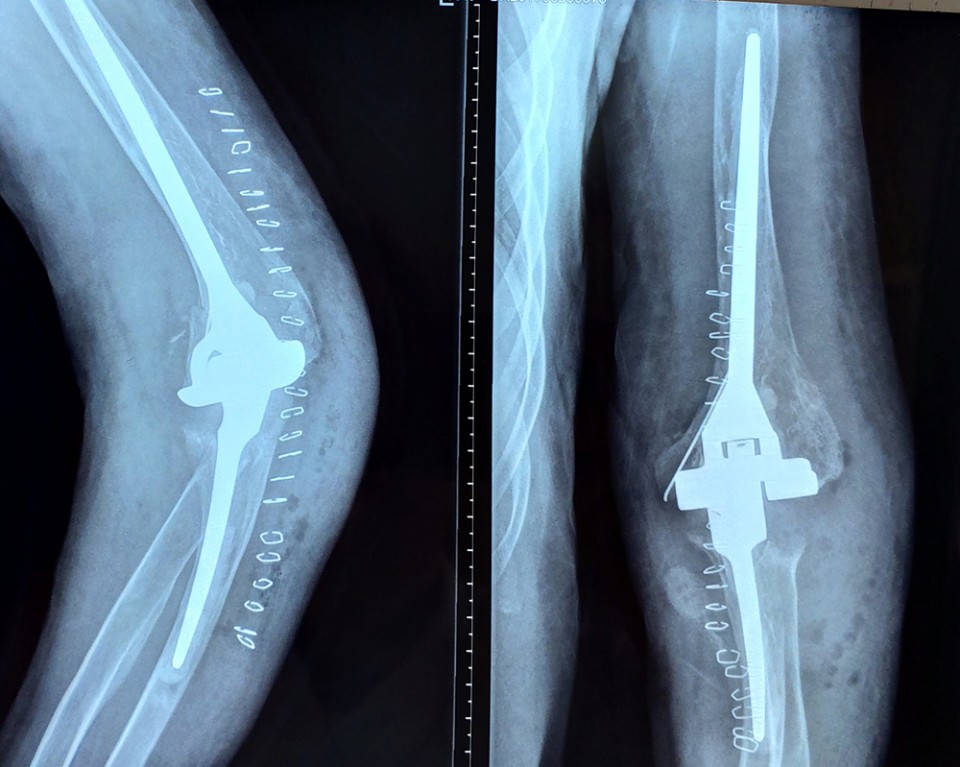

(手术后)

科室专家团队讨论并制定治疗方案,对患者实施双侧全肘关节置换手术。手术过程顺利,术后经专科护理团队的悉心护理和康复指导,患者双侧肘关节疼痛症状明显缓解,双肘关节的伸直和屈曲功能良好,满意出院。

我院肘关节置换术有自己特色,首先不破坏伸肘装置,不需要特殊重建,可以早期锻炼,术后关节功能好,并发症少。其次,通过改进技术,克服了肘关节置换术中骨水泥固定的难题,假体固定更牢靠,关节寿命更长久。(关节与显微修复外科 张金陵)